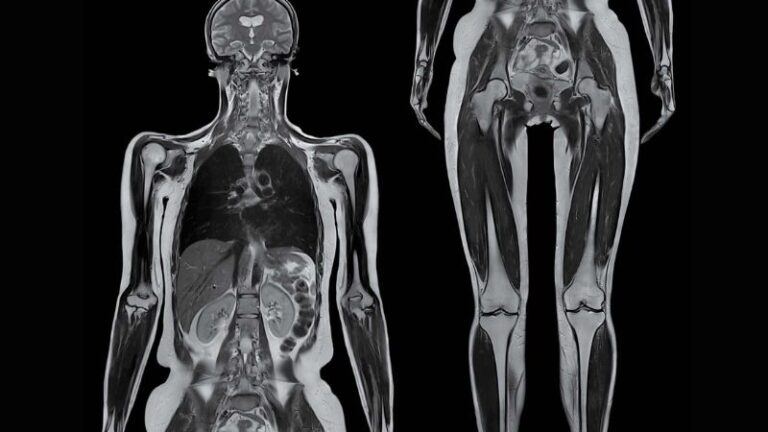

Total Body Imaging

Using 3T MRI technology

Welcome to Kansas City Advanced Diagnostic Imaging Services-Overland Park’s new destination for advanced brain and body imaging. Save time and get the detailed answers you need with our state-of-the-art 3T MRI, featuring 128 channels and a wide bore, which doctors prefer for superior structural detail. We also offer functional imaging for advanced neurological and psychiatric diagnostics. Your scans are interpreted by radiologists with extensive expertise in all imaging modalities. At Kansas City Advanced Imaging, our focus is on providing you with clarity, precision, and peace of mind with every scan.

Our advanced imaging systems provide physicians across specialties with the critical insights needed for effective intervention, surgical planning, and treatment tracking.